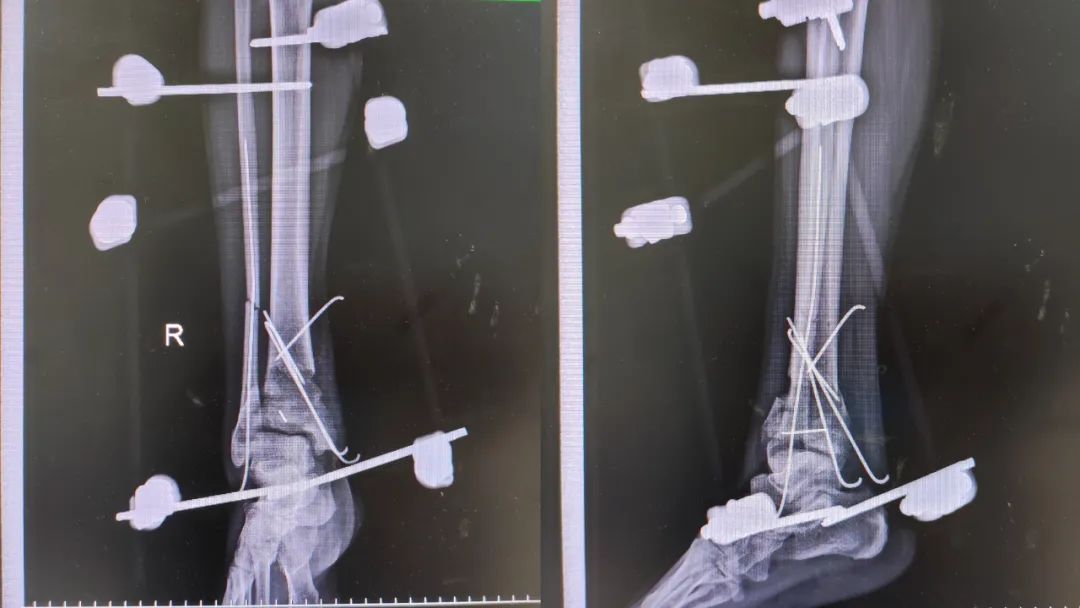

在腰硬联合麻醉、基础麻醉下行「右踝关节开放性骨折扩创探查骨折复位外固定架固定、VSD 负压引流术」,经过紧张有序的手术,患者安返病房。

外固定支架是应用固定针经皮穿入骨折端周围,并用各种形态的连接杆将固定针结合在一起的骨固定器械,有微创、可调节的特点。

外固定支架的优点:可以用于开放性骨折对骨折再次复位及固定,对骨血运破坏较小,对骨折软组织覆盖影响小。在感染风险高或者已有感染情况下可以降低感染的风险。